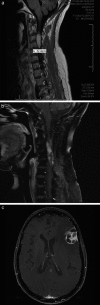

Results: 28 H3 K27M-mutant tumors were identified, with equal numbers of adults (13) vs. children (15). For adults, mean and median age was 52 years (range = 27 - 81 years), 2 decades older than a recently-published adult series. Tumors involved thalamic (adult = 7; pediatric = 7), spinal cord (adult = 4; pediatric = 2), pons (adult = 1; pediatric = 6), and hypothalamic (n = 1) sites. Other morphologies at presentation included pure GG (n = 3, pediatric) and PA (n = 1, adult). One adult and 1 pediatric patient each presented with leptomeningeal dissemination or developed leptomeningeal dissemination within 1 year after diagnosis, with transformation from PA or GG histology to glioblastoma. Mean survival was 9.3 (adults) vs. 8.9 (pediatric) months. Patients with tumors of other morphologies (GG, PA) did not enjoy extended survival.

Conclusion: H3 K27M-mutant tumors can affect patients at advanced ages, may show leptomeningeal dissemination at time of presentation, and "pure" GG or PA morphology is not rare. Regardless of patient age or tumor morphology, patients fare equally poorly. .